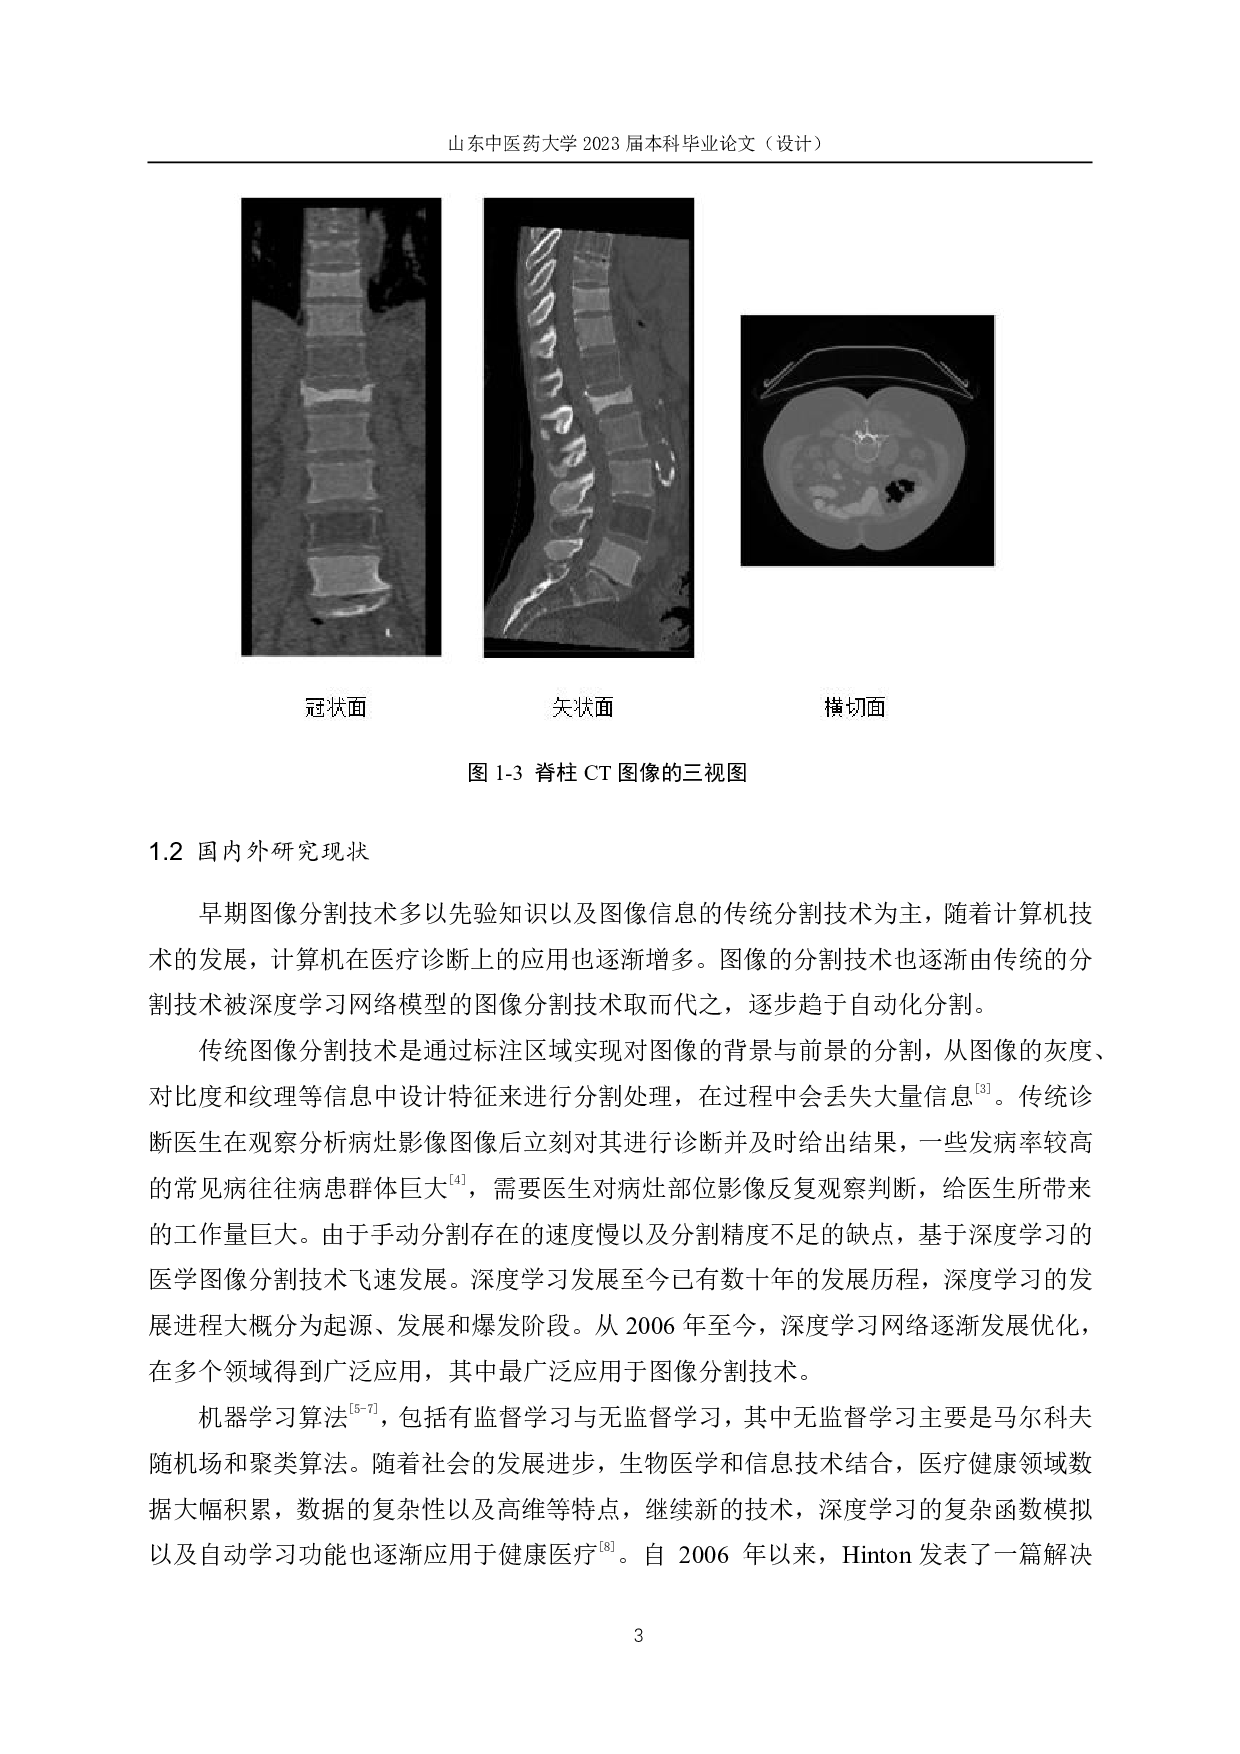

I 基于深度学习的脊柱图像分割技术研究 作者:史雨凡 山东中医药大学智能与信息工程学院2019级生物医学工程专业 指导教师:刘静 摘要 先天脊柱发育异常、脊柱退化性病变增生及脊柱损伤等是人体常见脊柱相关疾病。 近些年来,脊柱疾病发病率一直高居不下,并逐渐呈现年轻化趋势。脊柱分割可以有效 提高脊柱图像分析的效率,为医生进一步诊断检查奠定基础。传统医学分割技术,效率 普遍偏低,无法满足于当前医学发展的需求,深度学习网络模型的图像分割技术取而代 之。深度学习网络的图像分割技术作为医学检查的辅助工具,能够提高医生的诊断